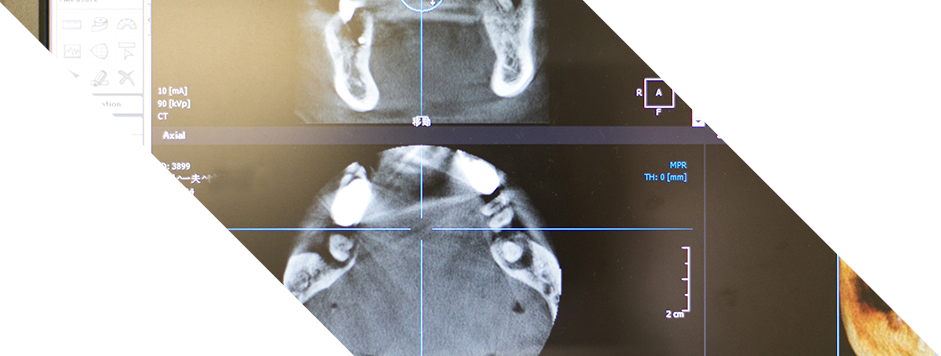

インプラント治療については、日本口腔インプラント学会の認定医資格を持つ歯科医師が対応しています。歯科用CTによる精密な診断をもとに、口腔内の状態を確認しながら、無理のない治療計画が立てられます。歯周病治療では、基本的なクリーニングから再生療法まで幅広く対応しており、検査によって状態を可視化しながら進められる点も特徴です。

そのほか、親知らずの抜歯などに対応する口腔外科、ライフステージに合わせた装置を提案する矯正歯科、入れ歯治療や咬み合わせの調整、顎関節の管理まで幅広く対応しています。歯科用CTや炭酸ガスレーザーなどの設備も活用されており、必要に応じた精密な診断が行われています。さらに、通院が難しい方に向けた訪問診療にも対応しており、地域のさまざまな世代を支える歯科医院です。

藤井寺駅北出口から徒歩1分の立地にある椿本歯科医院では、地域の皆様のお口の健康を支えるため、幅広い歯科診療が行われています。院内には歯科用CTをはじめとした設備が導入されており、外科的処置にも対応できる環境が整えられています。長年の診療経験を持つ院長が在籍し、対話を重視しながら診断と治療方針を丁寧に組み立てていく姿勢が特徴です。

インプラント治療においては、30年以上の臨床実績を持つ口腔外科出身の院長が担当し、骨の状態に応じた精密な検査と計画をもとに治療が行われます。歯周病や虫歯の治療では、進行段階に応じた処置を施すとともに、日々のケアについてのアドバイスも行われています。親知らずの抜歯を含む口腔外科領域では、これまでに2,000本を超える抜歯実績があり、がんなどの口腔内病変にも対応しています。矯正歯科では、ワイヤー矯正に加えてインビザラインによるマウスピース矯正も導入されており、生活スタイルに合わせた矯正が可能です。

インプラント治療では、骨の状態に応じた複数の手法を取り入れ、CTによる正確な診断とともに、安全性に配慮した処置が行われています。予防治療では、プロによるクリーニング(PMTC)や患者様ごとの生活習慣に合わせたブラッシング指導を通じて、むし歯や歯周病の予防に取り組んでいます。小児歯科では、お子さまに「怖くない場所」と感じていただけるよう配慮し、安心して受診できる環境を重視しています。小児矯正では、噛み合わせの発育や顎の成長に着目し、将来的な歯並びの改善にもつなげています。